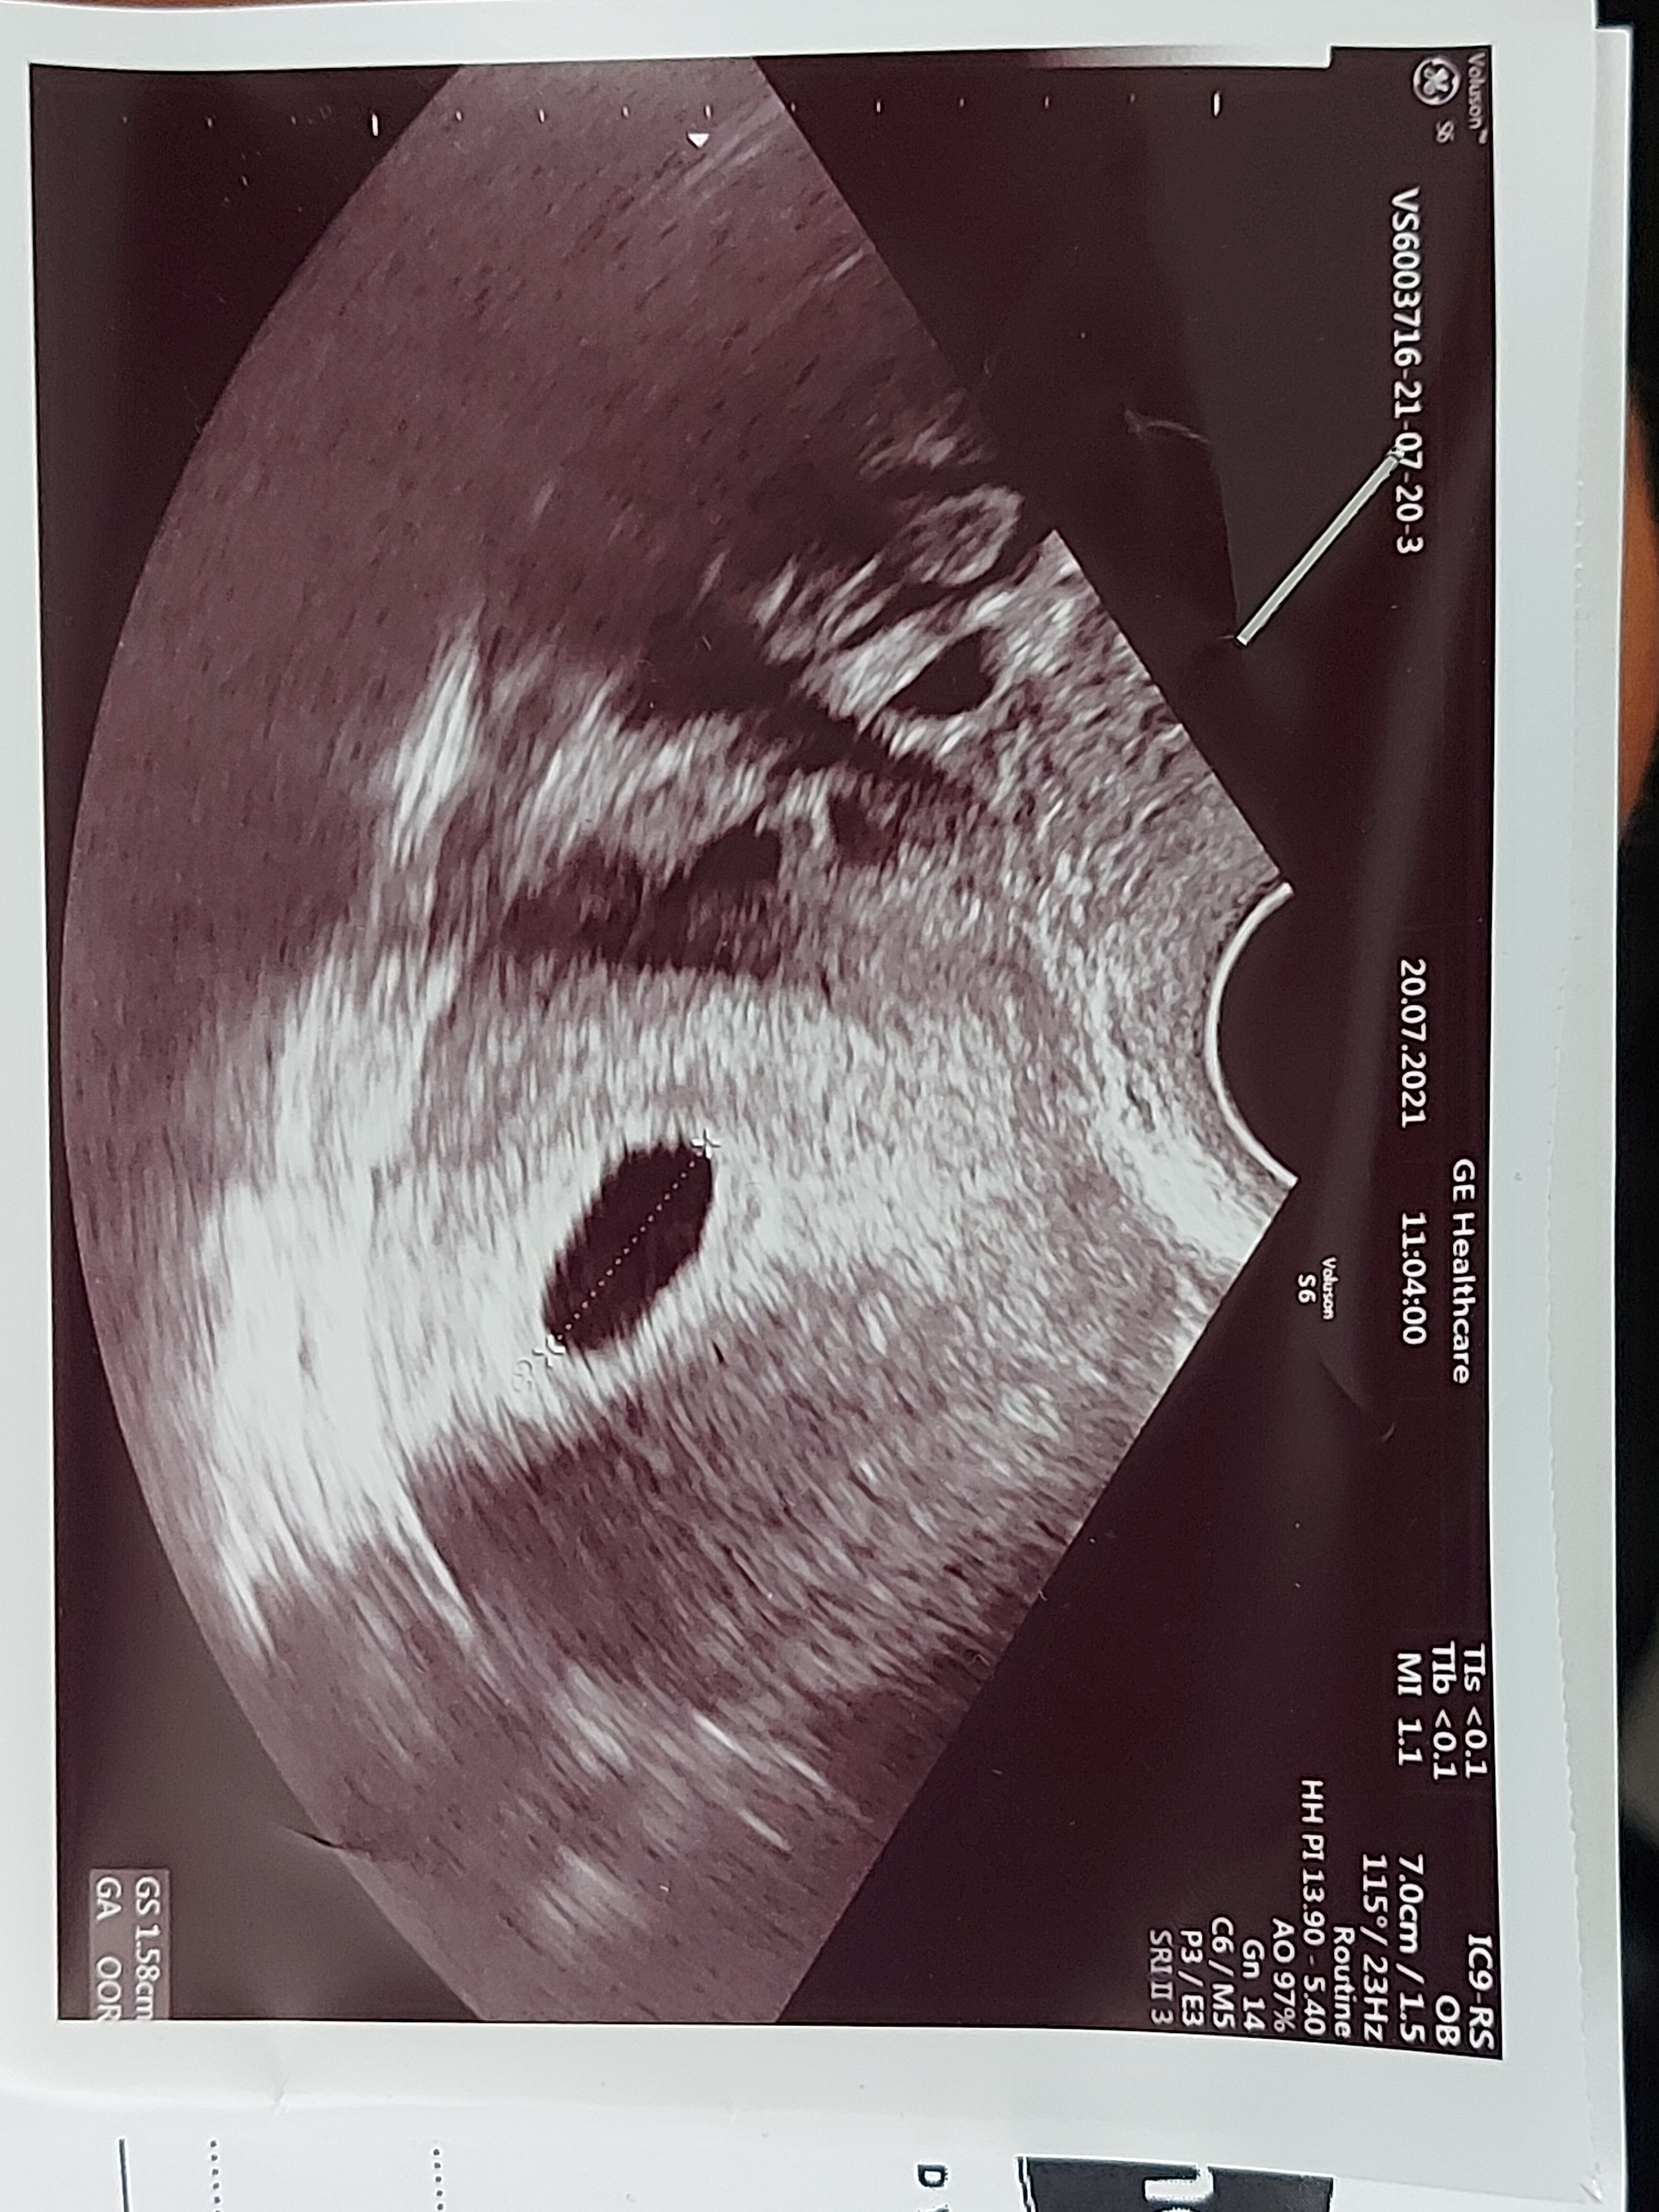

Witajcie jestem tu nowa.jak wynika z obliczeń jestem w 6 tygodniu ciąży.Dwa dni temu byłam u ginekologa który stwierdził ciąże.Jednak nie pokazał mi płodu jego badanie było szybkie i niewyraźne stwierdził że to jeszcze wcześnie i kazał przyjść za 10 dni.Bardzo się boje ponieważ naczyrałam się że w tym czasie wyraźnie powinien być zarysowany płud i bez problemu powinno być go widać nie wiem co robić czy zmienić lekarza czy czekać na następną wizytę do mojego pytania dołączam zdjęcie z usg

Po pierwsze - w którym tygodniu ciąży dokładnie jesteś? Bo wiele osób podaje albo zaczęte albo skończone. Druga rzecz - u Ciebie na USG widać dopiero sam pęcherzyk (ulokowany w macicy więc wiadomo, że nie pozamaciczna) więc wizyta za 10 dni jest wskazana by może już wtedy zobaczyć zarodek z serduszkiem. Poza tym o płodzie można mówić po 11 tygodniu ciąży...